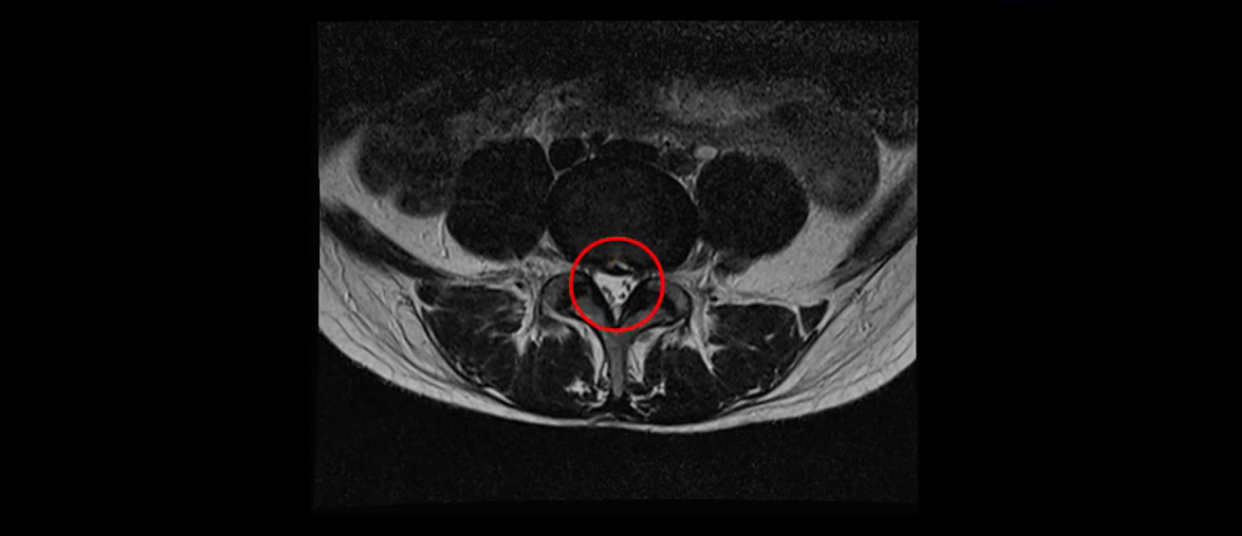

이분 MRI를 보시면 두 마디의 퇴행성디스크가 있습니다. 그리고 디스크가 조금씩 밀려 나와 있고요. 그런데 디스크 탈출 정도는 두 마디 다 심하지 않습니다. 4번 5번에는 디스크 탈출이 약간 있고,

척추관협착도 약간 진행이 되고 있고요.

5번 1번은 디스크 탈출이 가운데 쪽으로 살짝 있습니다.

중요한 것은 이 정도 경미한 탈출과 협착으로는 양쪽 다리가 저리고 아플 수가 없습니다.

그리고 만약에 이 디스크가 급성으로 찢어진 것이라면 아주 심한 디스크성 통증이 있겠죠. 기침이나 재채기를 하면 심하게 아프고 허리를 조금만 구부려도 아주 날카로운 통증들이 생길 겁니다. 그런데 이분은 이런 증상이 전혀 아닙니다. 디스크의 돌출 정도와 협착이 전혀 심하지 않기 때문에 이분이 가지고 계신 양쪽 다리 저림, 특히 이분은 누워있을 때도 양쪽 다리가 저리다고 하는데, 디스크 때문에 그런 증상은 생길 수가 없습니다. 또 이 디스크는 오래된 디스크, 이미 찢어진 섬유륜이 아문 디스크이고, 그러니까 이분은 기침이나 재채기를 못하는 증상이 없는 거죠. 그 다음에 허리를 구부릴 때 뻐근한 증상은 있지만 아주 날카로운 통증은 없습니다.

이분 MRI를 보시면 퇴행성디스크가 있고 약간의 협착이 있지만 이 정도의 퇴행성디스크와 협착으로는 신경이 눌려서 양쪽 다리가 저리고 아픈 증상이 나올 수가 없습니다. 그래서 MRI와 이 환자분의 다리 증상이 매치가 안 된다고 하는 의사들이 많은 겁니다.